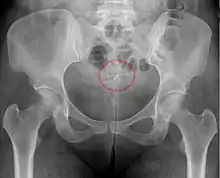

Mirena IUD visible on pelvic radiograph.

The hormonal IUD is a small 'T'-shaped piece of plastic, which contains levonorgestrel, a type of progestin.[23] The cylinder of the device is coated with a membrane that regulates the release of the drug.[69] Bayer markets Skyla as Jaydess in the United Kingdom.[70] Jaydess releases six micrograms per day and lasts for three years.[71] In comparison, oral contraceptives can contain 150 micrograms of levonorgestrel.[45] The hormonal IUD releases the levonorgestrel directly into the uterus, as such its effects are mostly paracrine rather than systemic. Most of the drug stays inside the uterus, and only a small amount is absorbed into the rest of the body.[45]